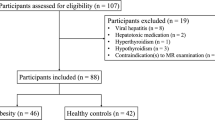

From September 2021 to April 2023, 69 subjects with obesity were recruited from the Weight Loss and Metabolic Surgery Department of the Fourth Affiliated Hospital of Harbin Medical University. Clinical data and laboratory examinations were collected at admission, and cardiac and abdominal scans were performed using a 3.0 T MRI. The visceral fat area was significantly increased (AVFA ≥ 150 cm2) in the study group (41 subjects), and the AVFA was slightly increased (100 cm2 ≤ AVFA < 150 cm2) in the control group (28 subjects). The exclusion criteria included contraindications to MRI, such as large abdominal circumference and claustrophobia, history of heart disease, and history of alcohol or drug use leading to NAFLD. All subjects were not obese due to abnormal hormone levels. The characteristics of the subjects are shown in Table 1.

Before collecting clinical samples, all patients provided written informed consent. This study was conducted in accordance with the standards established by the Declaration of Helsinki. The study protocol was approved by the Ethics Committee of the Fourth Affiliated Hospital of Harbin Medical University. Fig. 1 illustrates the selection and exclusion of subjects.